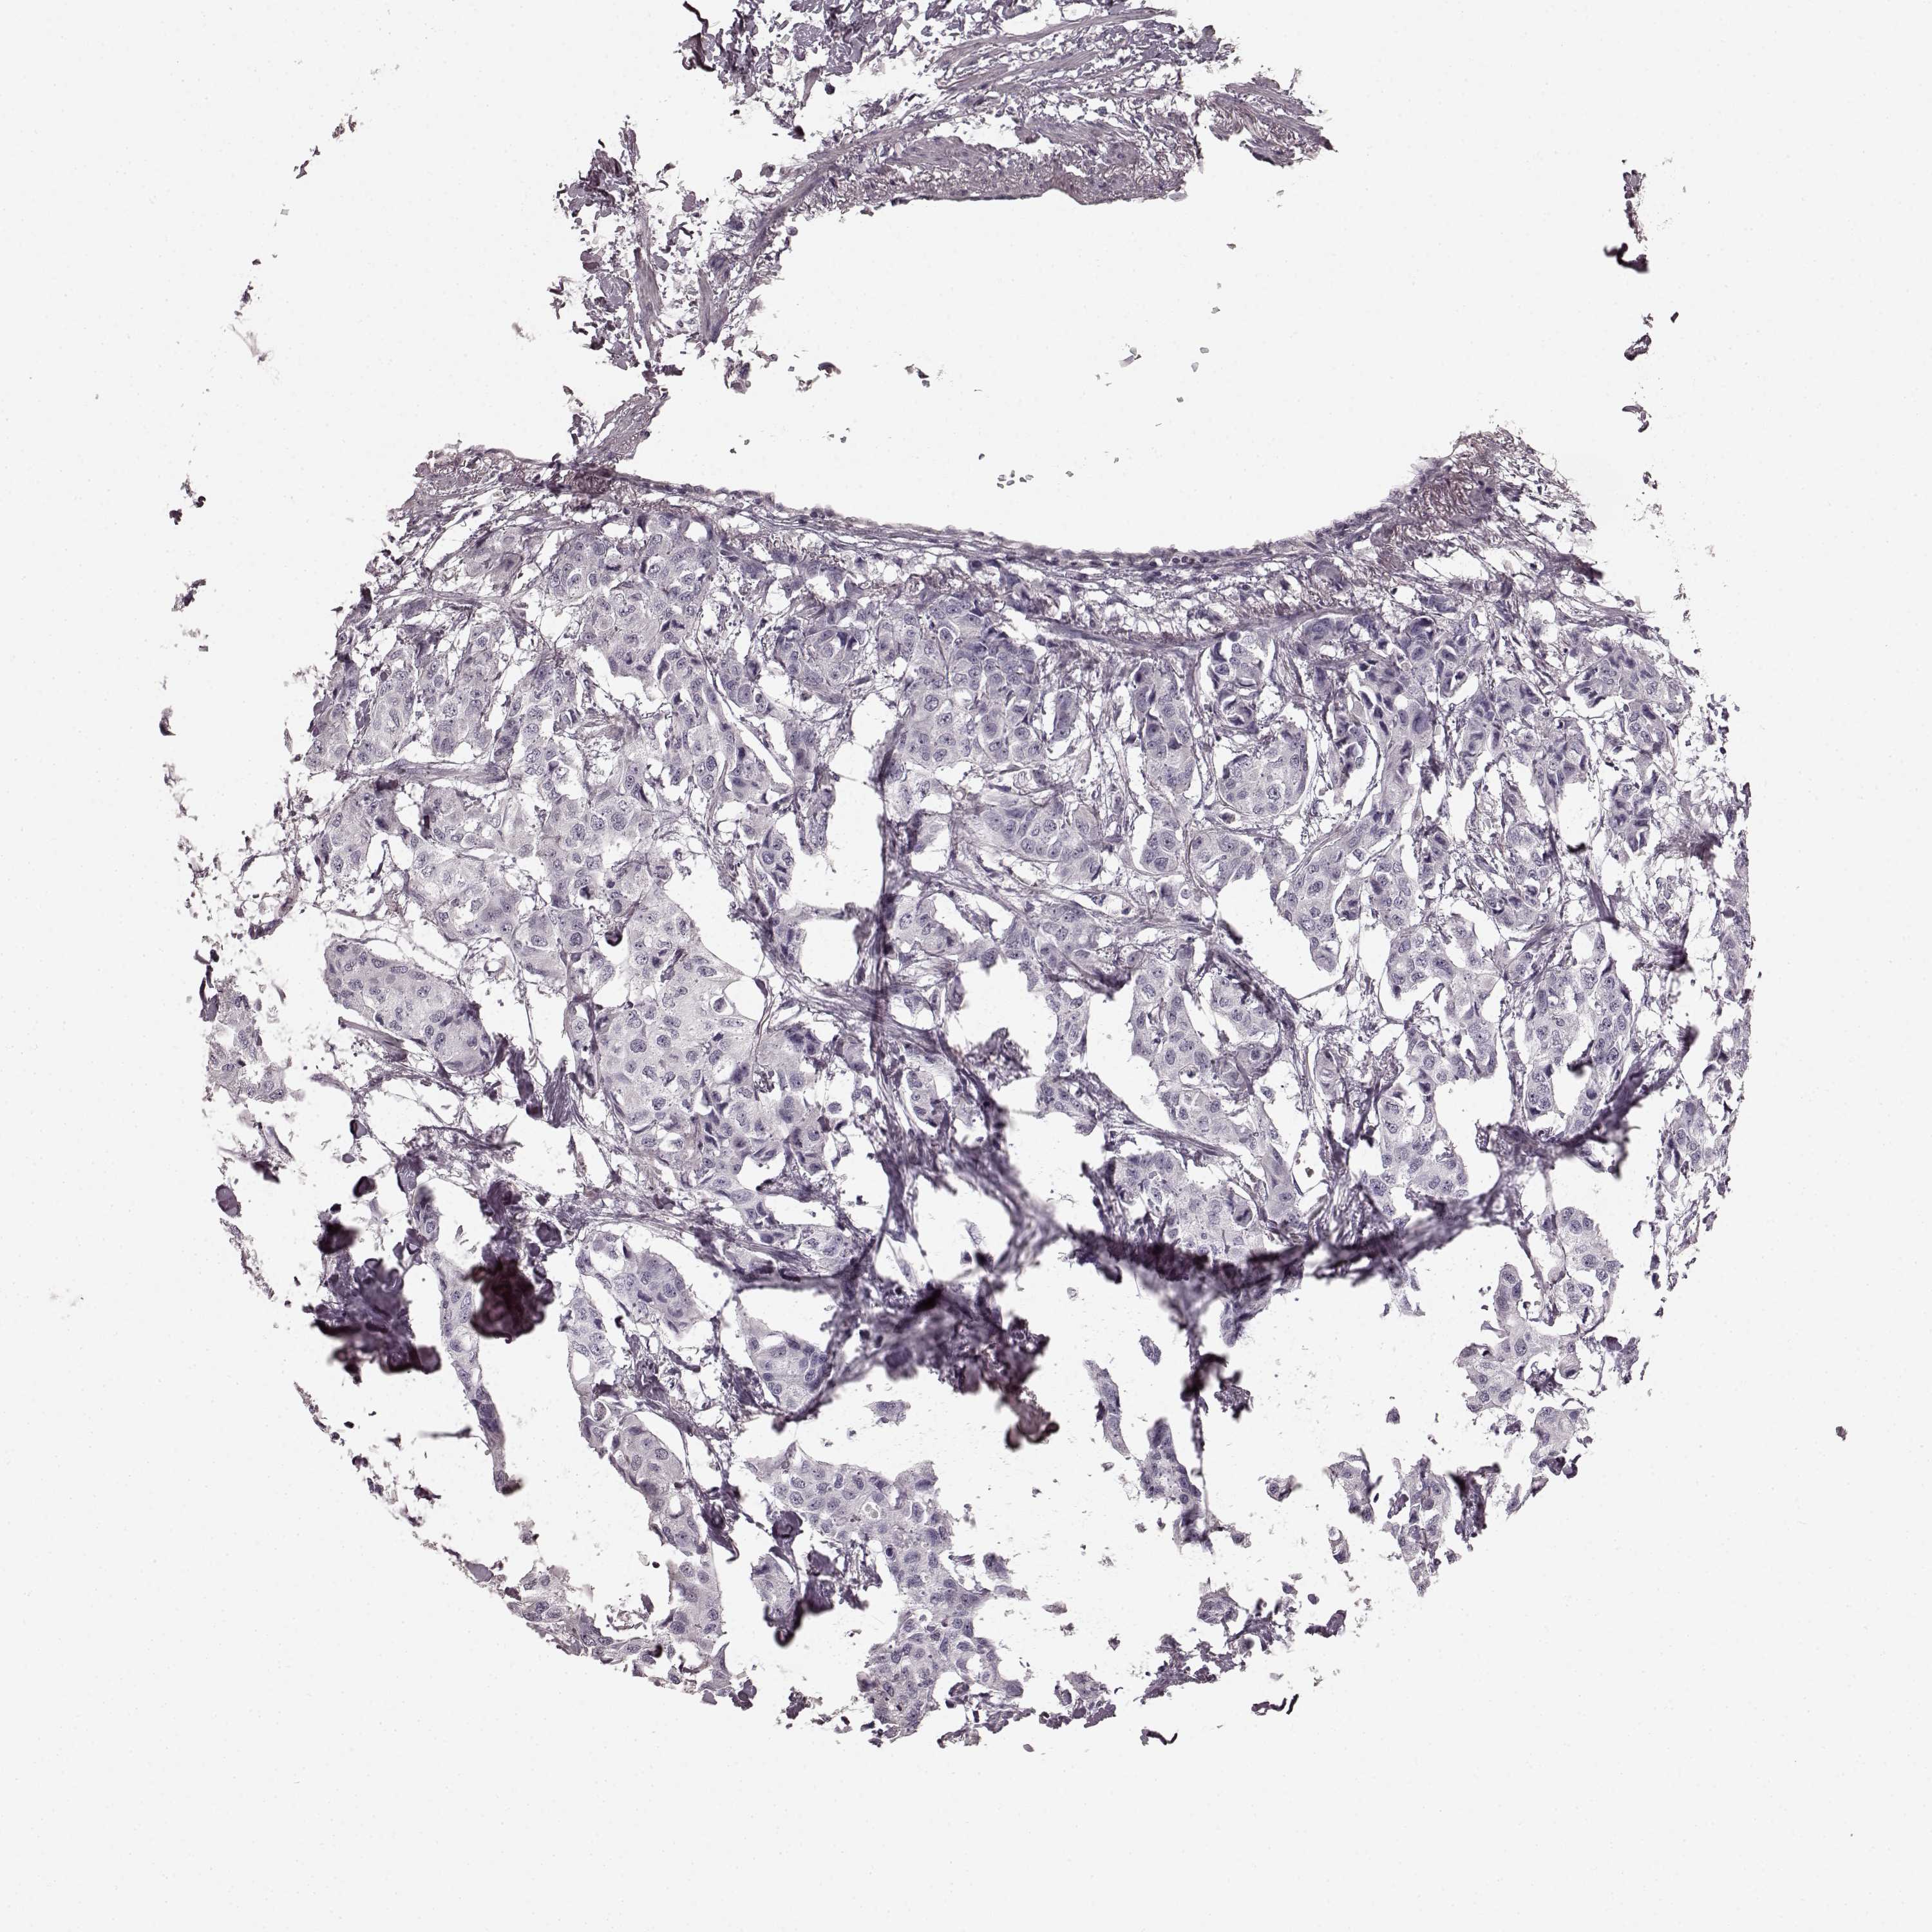

CANCER BREAST CANCER Show tissue menu

BRCA TCGA BRCA VALIDATION PROTEIN EXPRESSION